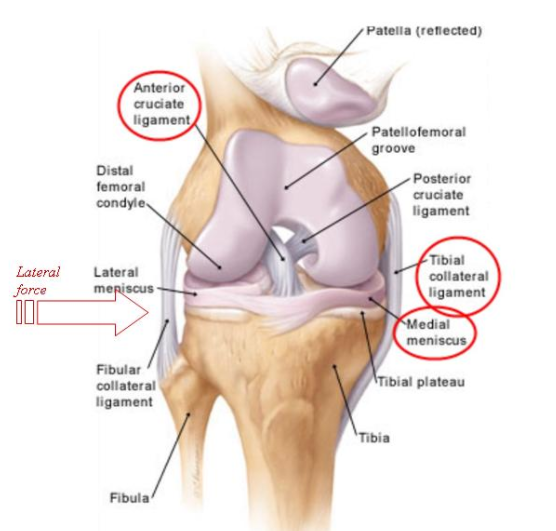

A lateral blow to the knee causes which triad of injuries classically?

Unhappy triad is an injury to ACL, MCL, meniscus.

Analysis during 1990s indicated that this ‘classic’ O’Donoghue triad is actually an unusual clinical entity among athletes with knee injuries.